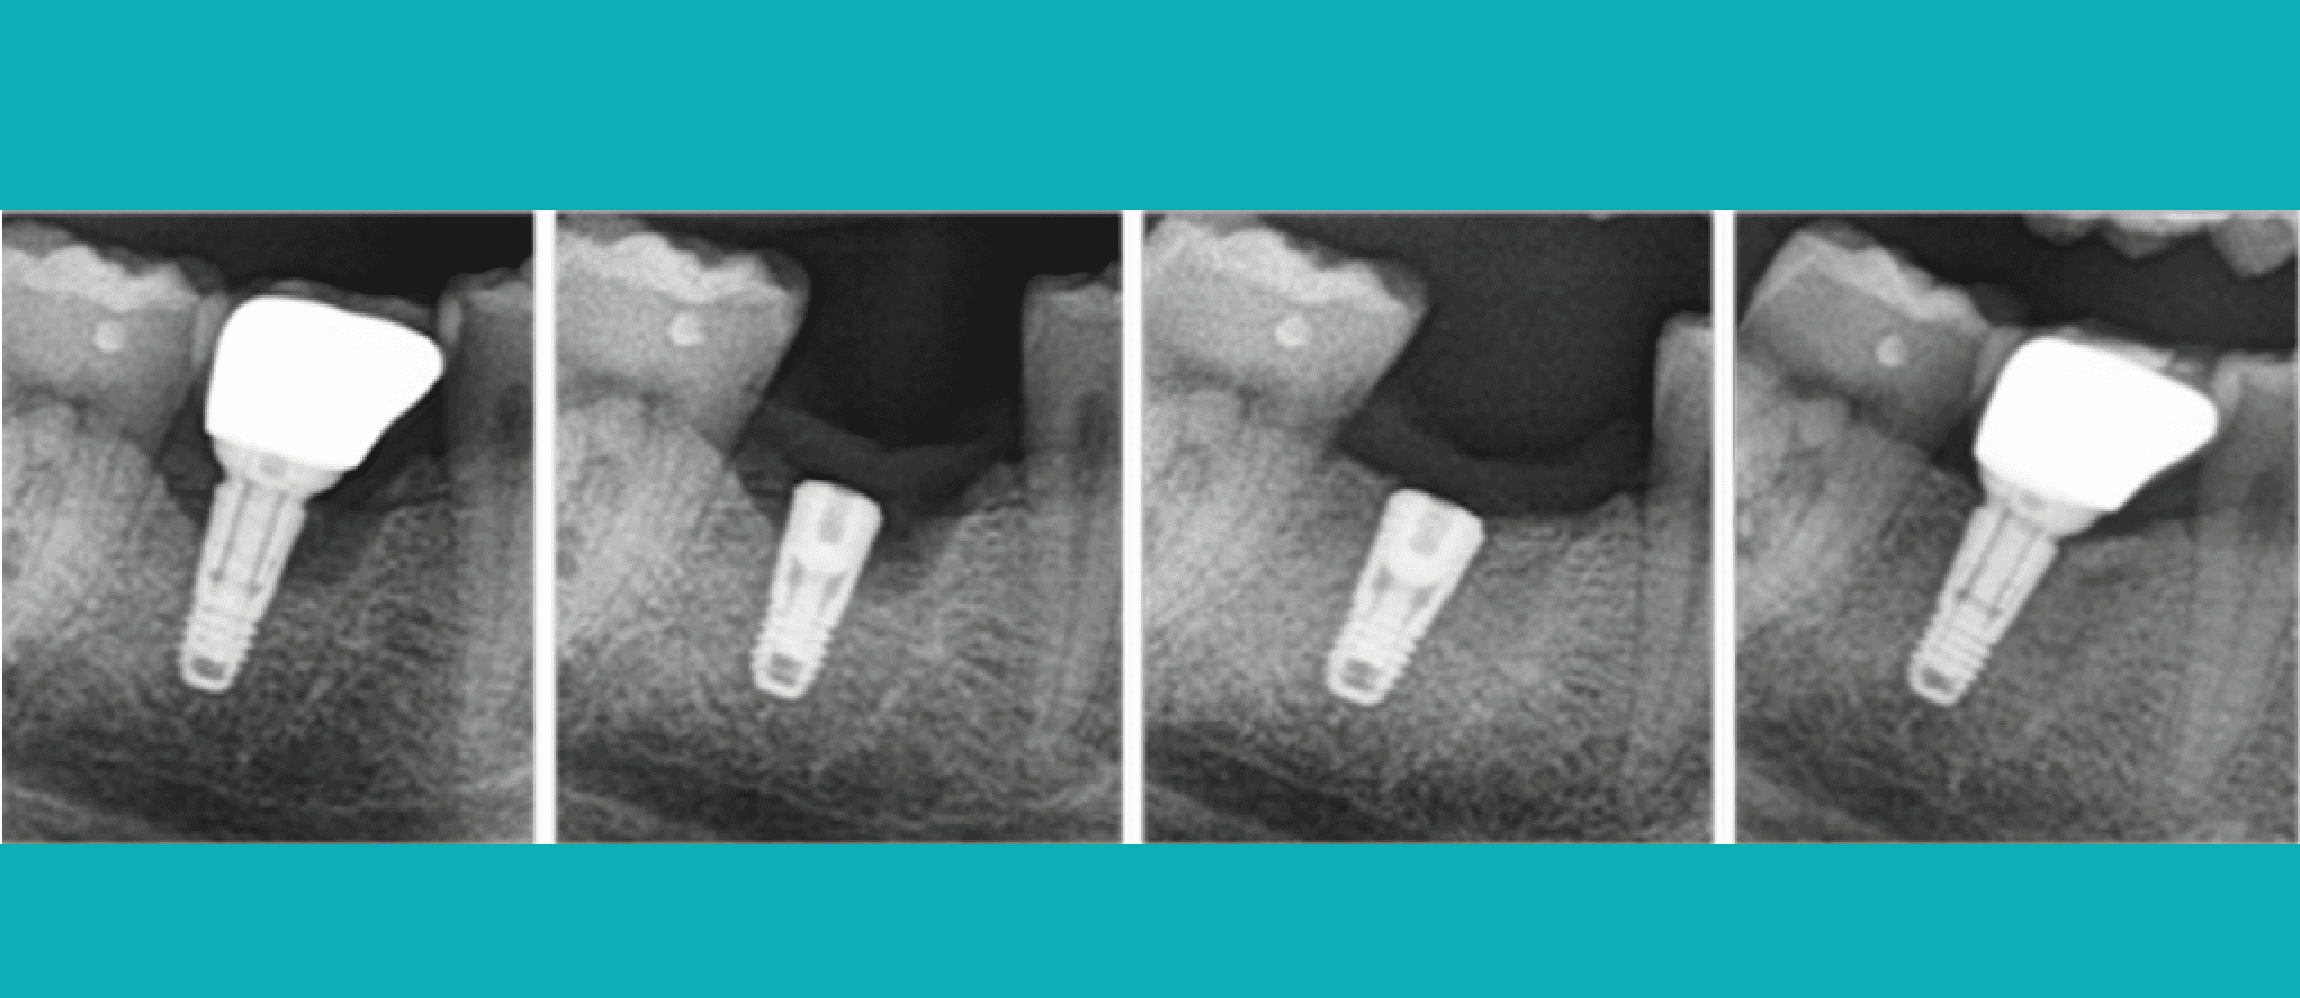

- Définition, classification, critères diagnostiques (radiologiques + cliniques)

- Péri-implantite légère vs modérée vs sévère